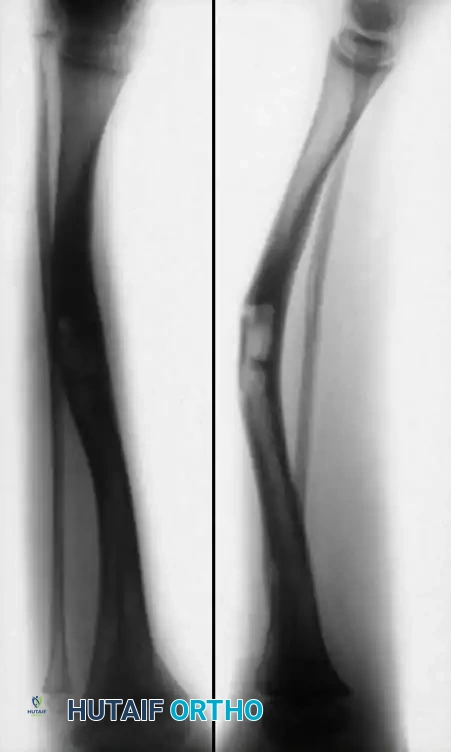

Radiographic follow-up showing incorporation of bone graft and maintenance of alignment following intramedullary fixation.

Even when union is achieved, the tibia remains biologically abnormal. The medullary canal often remains narrow, and the cortex lacks normal remodeling capabilities. Refracture is a constant threat until skeletal maturity.

Long-term follow-up imaging demonstrating the persistent risk of refracture or hardware migration in the biologically compromised tibia, necessitating prolonged orthotic protection.

Therefore, once union is obtained, the limb must be protected in a patellar tendon-bearing (PTB) brace or AFO until the child reaches skeletal maturity. Parents must be extensively counseled that limb salvage is a childhood-long commitment, often requiring secondary procedures for hardware exchange, management of leg-length discrepancies (via epiphysiodesis or lengthening), and correction of residual angular deformities.